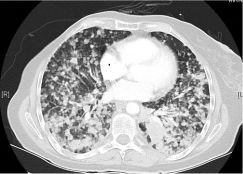

一位77岁的女性患有EPS15-NTRK1 IV期非小细胞肺癌,我们可以看到她的双肺满是病灶,并且出现了肝脏和脑转移,可以说是非常非常晚期了,

肺靶病变达到缓解,我们可以明显的看到前后的图像,病灶明显缩小了,

脑转移病变显示缩小了95%!

初始, 2018年6月             3周期 2018年8月